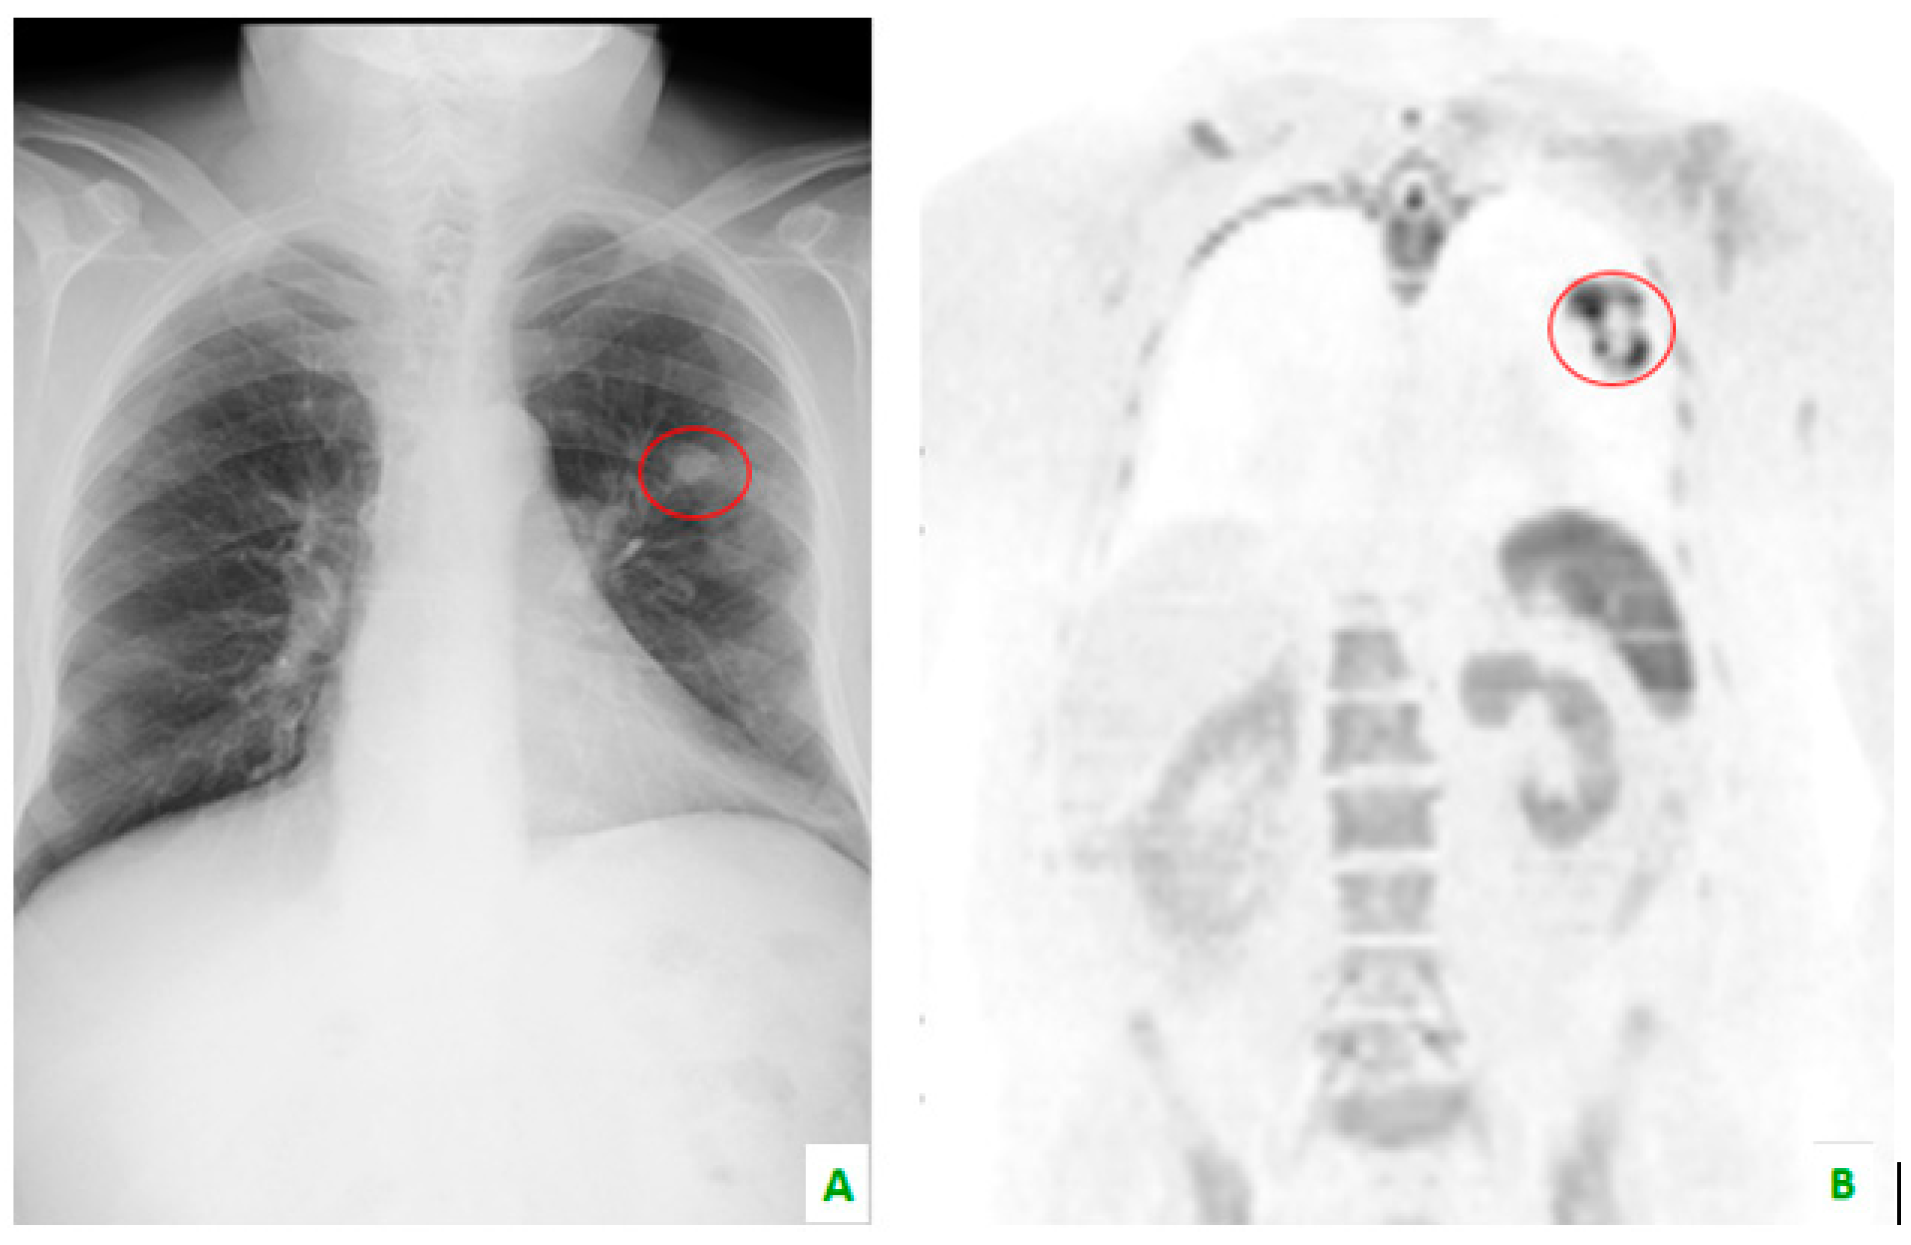

Figure 3. (A) This chest X-ray reveals, in the red circle, a lung tumor which is also visible in (B) whole body magnetic resonance imaging with diffusion-weighted imaging (WB-MRI-DWI) in the coronal plane, in the red circle.

Skeletal metastases, which are predominantly osteolytic, localize in the spine in 50% of patients. This the most common area of localization, followed by the ribs (27.1%), ilium (10%), sacrum (7.1%), femur (5.7%), and the humerus, scapula, and sternum (2.9%). This is according to a retrospective study by Tsuya et al. [27] (Figure 3, Figure 4 and Figure 5).